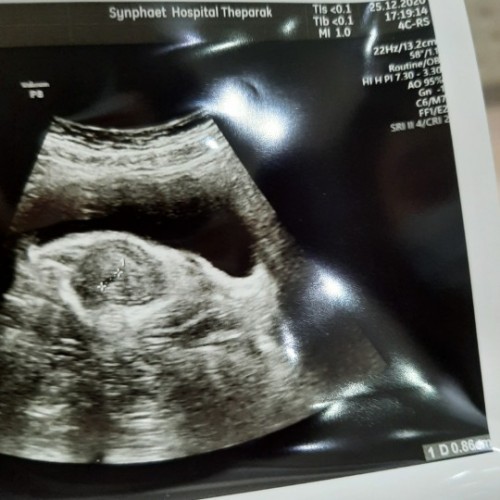

ตั้งท้องได้6สัปดาห์อัลตร้าซาวด์วันนี้หมอบอกว่าเห็นแต่ถุงตั้งครรภ์ยังไม่เห็นน้องค่ะ นัดอัลตร้าซาวด์ใหม่เดือนหน้า